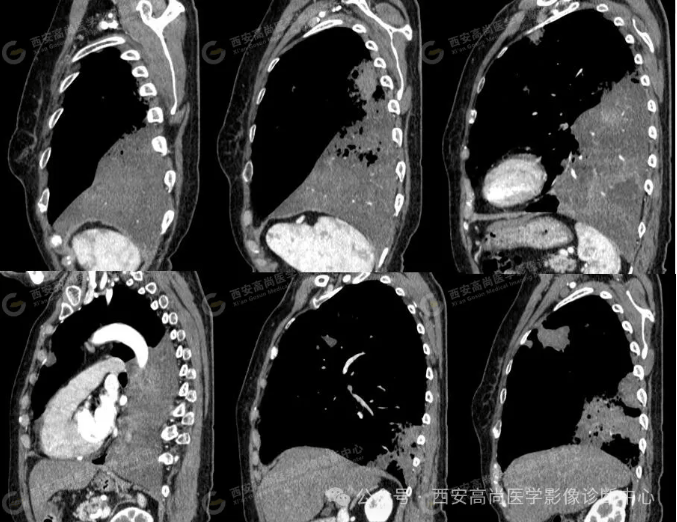

pet/ct病例—肺粘液腺癌,历经3年余终确诊【西安高尚医学影像诊断中心